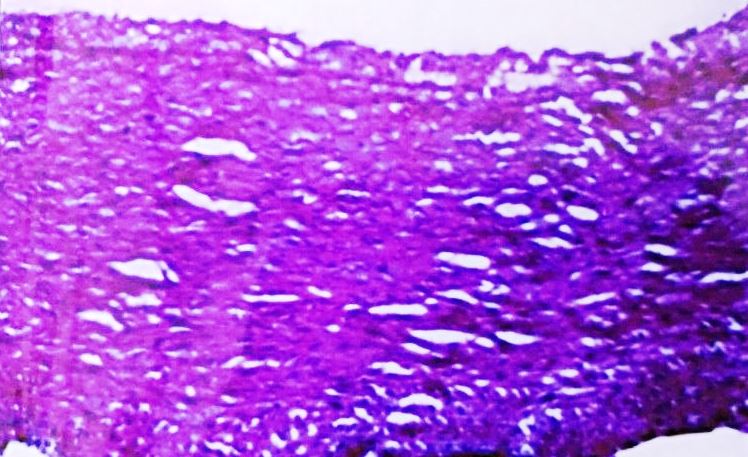

The histopathological examinations were also performed in the ascending aorta and coronary artery in high cholesterol animal diet group and high cholesterol animal diet accompanied with C. verum extract group when compared with control (fig. 3-10).

Asending Aorta

Histological study showed that control group had completely normal arteries without any lesion in intima or media. In our study athero fed rabbits showed well developed atheromatous plaque protruding in to the lumen of the aorta. There were many foamy (lipid-laden) macrophages and dense fibrous tissue layer in the plaque could be seen. Media was also showing foam cell. The animals consuming the C. verum along with high cholesterol, the severity of lesions were significantly reduced, three layers of aortic wall were distinct, and only few lipid-laden cells were present in the medial layer when compared with the rabbits consuming the high cholesterol diet (group II) (fig. 3-6).

Fig. 5: Ascending aorta of rabbit-Athero Diet+C. verum 200 mg concurrent (120 d)

Fig. 6: Ascending aorta of rabbit-Athero Diet+C. verum 300 mg concurrent (120 d)